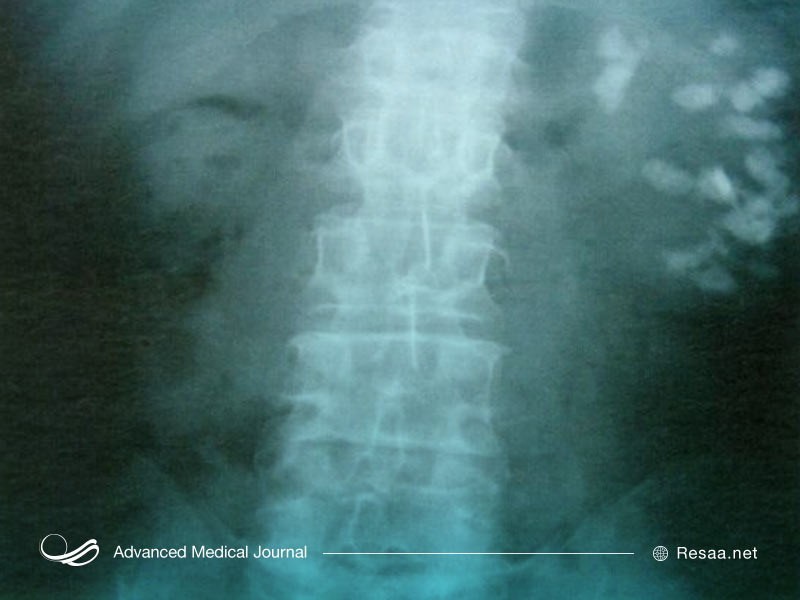

- اشعه ایکس شکم: تشخیص نفروکلسینوز، سنگهای ادراری.

- سونوگرافی: حساسیت بیشتری نسبت به رادیوگرافی معمولی دارد و میتواند در برخی از سناریوهای بالینی نسبت به سی تی اسکن برتر باشد (به عنوان مثال نفروکلسینوز همراه با هیپوپاراتیروئیدیسم).

- سی تی اسکن: در تشخیص کلسیفیکاسیون موثرتر است و میتواند برای تمایز رسوبات مدولار و قشر بیرونی مغز استفاده شود.

به منظور تشخیص بالینی روش رادیولوژیک لازم است و این بیماری در حدود 0.1٪ از عکسهای رادیولوژی کلیه مشخص شده است. این وضعیت با تجزیه و تحلیل میکروسکوپی در حدود 10٪ از کالبدشکافیها تشخیص داده میشود.